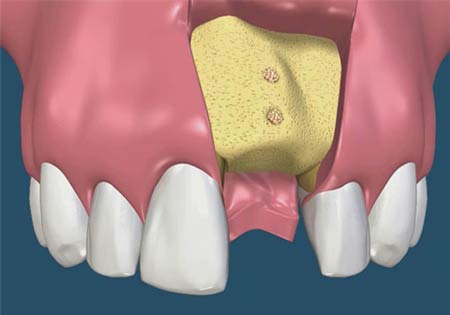

جراحی پیوند استخوان

در صورتی که در اثر بیماری لثه به استخوان آسیب وارد شود، با تکنیک جراحی پیوند استخوان، بافت استخوان پیوندی برای جایگزینی بخش آسیبدیده استخوان استفاده میشود. تکههای کوچک استخوان (یا از استخوان خود فرد، یا از بانک اهداء استخوان و یا استخوان مصنوعی) در محلی که استخوان تحلیل رفته بود، قرار میگیرد. این پیوندها بهعنوان پایهای برای رشد مجدد استخوان و بازیابی استحکام دندان بکار میرود.